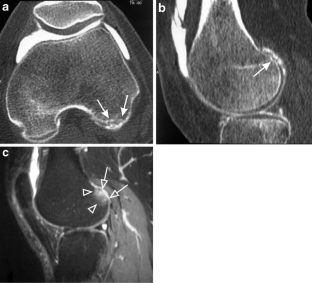

Subchondral impaction fractures of the non-weight-bearing portion of the lateral femoral condyle

Sixteen cases of intra-articular impaction fractures in a posterior, non-weight-bearing area of the lateral femoral condyle were diagnosed in patients with a mean age of 40. Eight were associated with recreational sports activities and 4 with repeated kneeling. There were no fractures documented in the non-weight-bearing aspect of the medial femoral condyles. Proposed underlying mechanisms for development of this type of fracture are presented.

Awareness, along with a high level of suspicion, that non-specific knee pain, especially in patients involved in athletic activities, could be due to intra-articular impaction fractures of the non-weight-bearing posterior aspect of the lateral femoral condyle is essential and MRI is the mainstay of diagnosis.

Fig. 3